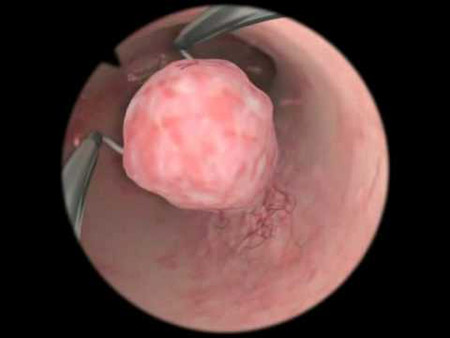

- Гинекологический осмотр с помощью зеркал иногда позволяет диагностировать новообразование, а иногда – предположить его наличие;

- Кольпоскопия – довольно информативный метод, но назначается нечасто;